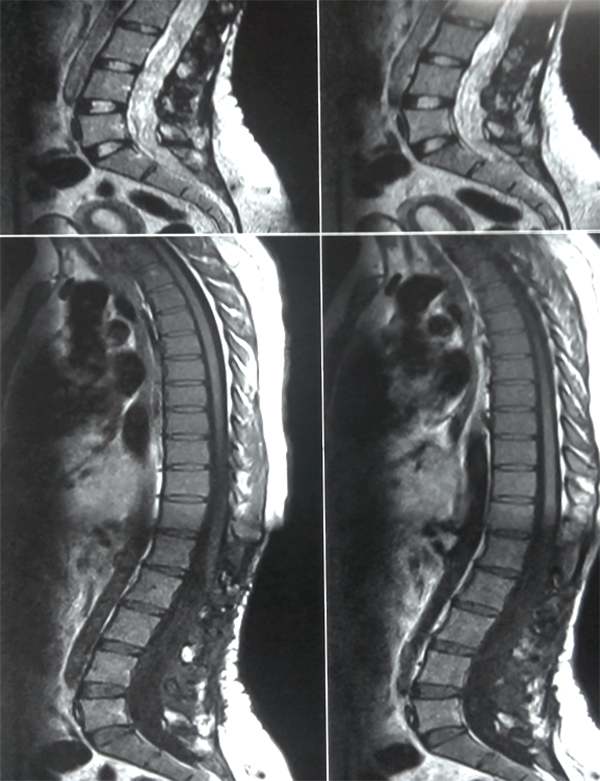

Es evidente que el límite entre el tejido medular y tumoral en las lesiones como los astrocitomas es indiscernible lo que dificulta la posibilidad de resección completa; en los tumores como los ependimomas esta diferencia es más franca y permite seguir un plano de disección seguro (Figuras 3, 4 y 5). Lo anterior condiciona nuestros resultados como han puntualizado diversos autores.5,8 El estado general previo a la cirugía requiere de una valoración juiciosa de las posibilidades de resección. Por ejemplo, el caso 12 (Figura 6) es una paciente portadora de Enfermedad de Von Hippel Lindau, Hemangioblastoma cervical biopsiado en otra institución del exterior del país, fijación de columna cervical y sindrome de Cushing por exceso de medicación corticoidea cuya cirugía debió suspenderse en dos oportunidades por la disminución de su capacidad ventilatoria. Con estos antecedentes y la delgada capa de tejido medular evidenciada intraoperatoriamente se optó por una resección subtotal. A los cuatro meses de la cirugía la paciente recuperó la marcha autónoma y demás parámetros clínicos.

Figura 6: Caso 12. Hemangioblastoma cervical. Ocupa la mayor parte del cordón medular marcado con círculo.

Figura 8: Caso 12. Enf de Von Hippel Lindau. Hemangioblastoma cervical. Se observa otra lesión a nivel del Culmen cerebeloso.